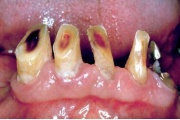

Vali sind huvitav pilt ja me näitame sellega seotud haigust ja sümptomeid